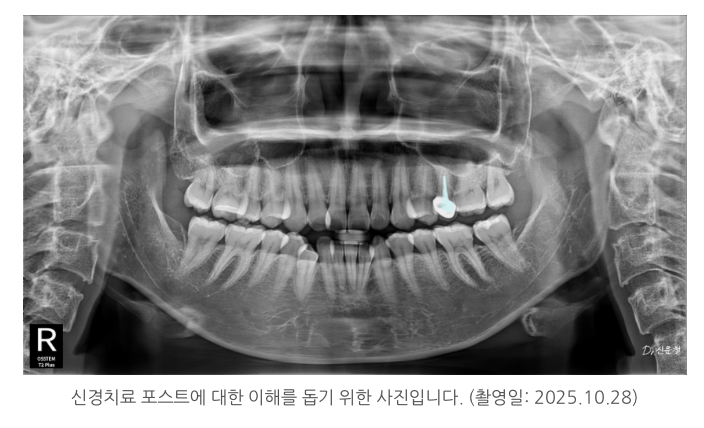

그래서 상태에 따라 기둥 보강(포스트)을 하고

그 위를 씌워 치아를 보호하게 됩니다.

[▼기둥 관련하여 함께 보면 좋은 글▼]

https://blog.naver.com/dasomdentalclinic/223930385601